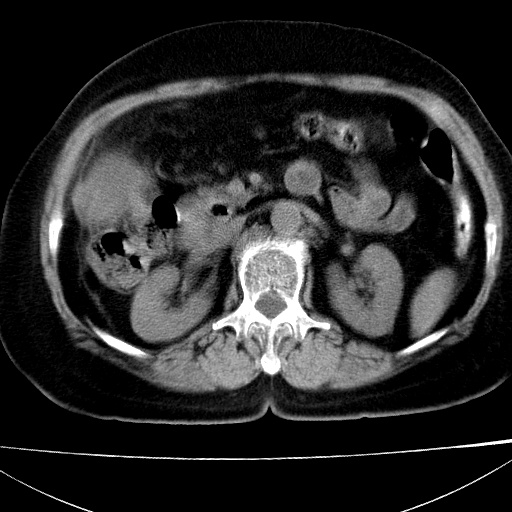

患者女74岁;右上腹胀痛1月,伴恶心,无发热;生活在疫水区。有术后病理及术后半年的追踪ct.

1)慢性血吸虫病(典型)。2)肝硬化。3)肝癌?4)胆囊炎。5)少量腹水。6)右侧少量胸腔积液。

支持.边缘见高密度线条样钙化影.

肝脏体积缩小,肝裂增宽,边缘不平呈波浪状,肝右叶见分隔状条索形钙化,亦见多结节低密度灶,边界不清,肝周可见少许液性暗区,胆囊增大内密度均匀,脾脏下缘低于脏脏的下缘,胸腔亦见液性暗区,余未见明显异常.

诊断:1肝硬化并慢性吸血虫病,脾肿大

2肝内占位,考虑肝癌可能性大,建议做增强

3胆囊炎, 4少量腹水及胸水

胆囊增大饱满,壁增厚。胆囊颈部见软组织密度影。临近肝右叶前段见片状低密度区,病灶下部见条状钙化,少量胸腹腔积液。意见:胆囊颈癌累及肝脏。

病人以胆囊癌手术的,病理结果为中分化腺癌。

现在看看肝右叶内圆形低密度影你们考虑什么呢?

肝内圆形低密度影考虑扩张的胆管

请看3mm重建像如下: